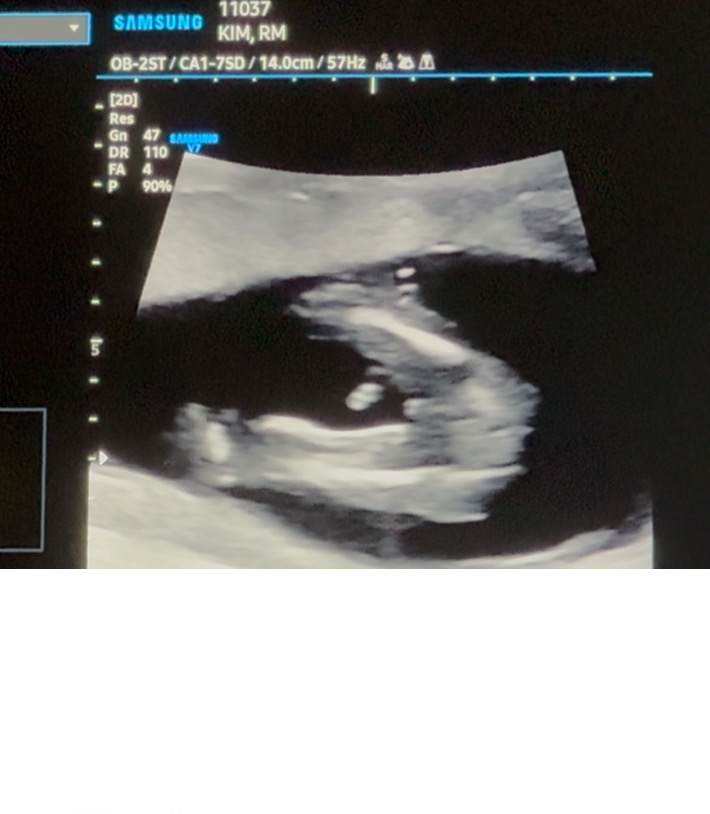

여아 확실할까용??

14주1일이에요! 밑에뭐가 없어보이는데 여자 백퍼일까요ㅠㅠㅠㅠ 아들바라는데 계속 딸이네용..🥲

고츄....있는데용...

스샷여러개찍엇는데 올린거는 밑에먼가 잇어보이네여ㅠ다른건또 암것도없는데말이죠